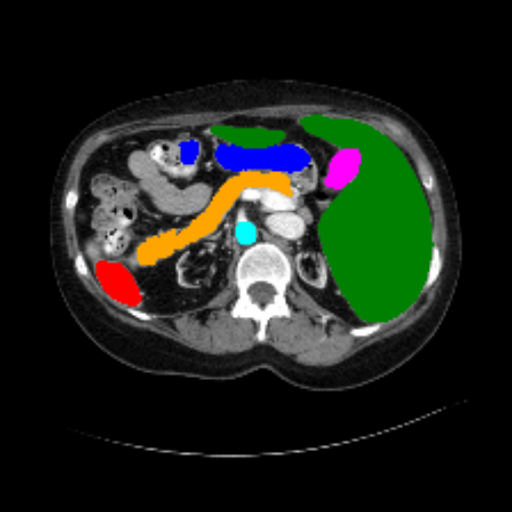

Across BTCV, ACDC, and ISIC17, the comparison methods exhibit varying performance depending on the task and class. For instance, Mamba-Unet struggles to segment multiple organs in BTCV, even misclassifying certain classes as others. In the ACDC dataset, both TransUnet and Mamba-Unet perform poorly in segmenting the three classes. In the last column (ISIC17), Swin-Unet oversegments the skin lesion compared to the ground truth. Unlike the comparison models, our approach consistently delivers effective segmentation across different tasks and datasets.

These qualitative findings further reinforce the quantitative results presented in the experimental section, demonstrating the effectiveness of our MambaCAFU model in handling binary and multi-class segmentation across diverse medical imaging modalities and tasks.

Slice GT Unet TransUnet Mamba-Unet Swin-UMamba MambaCAFU-V1

Figure 3: Visual comparison of segmentation examples from Synapse (first two examples), BTCV (3-4 examples), ACDC (5th example) and ISIC17 (last example). Columns: input slice, ground truth, Unet, TransUnet, Mamba-Unet, Swin-UMamba, and MambaCAFU-V1.